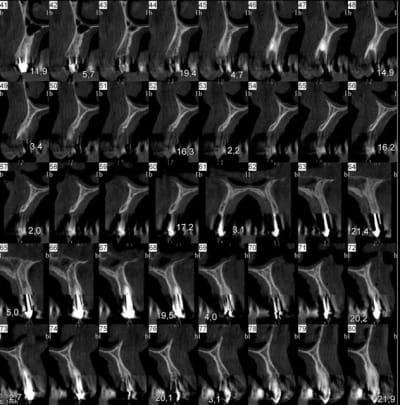

Bonjour, je sèche sur un cas, dont je vous joint le scan.

Malheureusement, j'ai peu d'épaisseur osseuse en antérieur; j'ai par ailleurs peu d'expérience en greffe ou expansion : je n'en connais pas les limites et ne sais donc pas comment aborder mon cas...

Faut voir l'expert de l'expansion xbK mais je pense que l'espace intercortical apical est trop faible; Je gérerai par une greffe d'apposition bloc osseux fixé en premier.

+1 pour la greffe...en plus j'ai l'impression d'un manque en hauteur également...

Ce qui me gène, c'est la finesse de l'os dans certaines zone ou y'a guerre plus de 2,5 mm et j'imagine mal ouvrir ça sans risquer de tout fracturer.